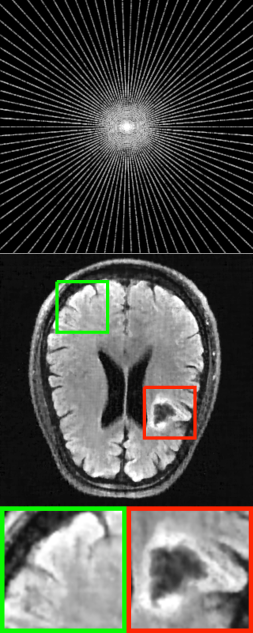

Refer to caption

Figure 1: Implicit neural representation for undersampled MRI reconstruction with radial sampling.

For ease of explanation, we restrict ourselves to a 2D MR imaging task. A general 3D reconstruction scheme would be discussed later. Fig. 1 illustrates a schematic description of the proposed method.